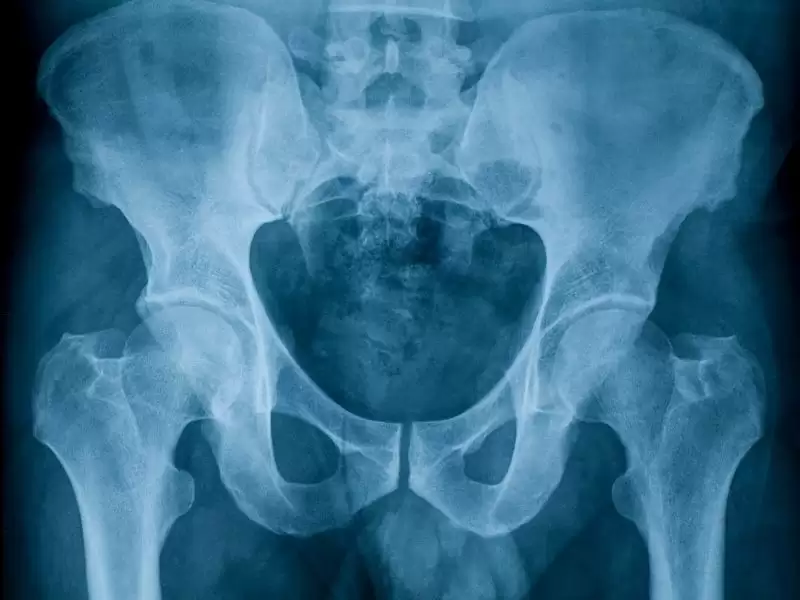

Kalça Yüzey Kaplama (Resurfacing) Protezleri

Son yıllarda geliştirilen bu yeni yöntem genç-aktif hastaların kalça sorunlarında çok önemli bir yaklaşım sağlamıştır. Klasik protezlerde uyluk kemiği başı kesilmekte ve protez uyluk kemiğinin içine çakılmaktadır. Yüzey kaplama protezlerinde ise baş kesilmeden biçimlendirilmekte ve protezin alt kısmı başa kemik çimentosu ile yapıştırılmaktadır.

Yuva kısmı da klasik protezlerden (yuva 2 parçadır) farklı olarak tek parçadır ve her iki yüzey de metaldir. Klasik protezlerde yine baş çapları 28-32-36 mm çaplarındadır. Yüzey kaplama protezleri ise 44mm den başlar ve büyür.